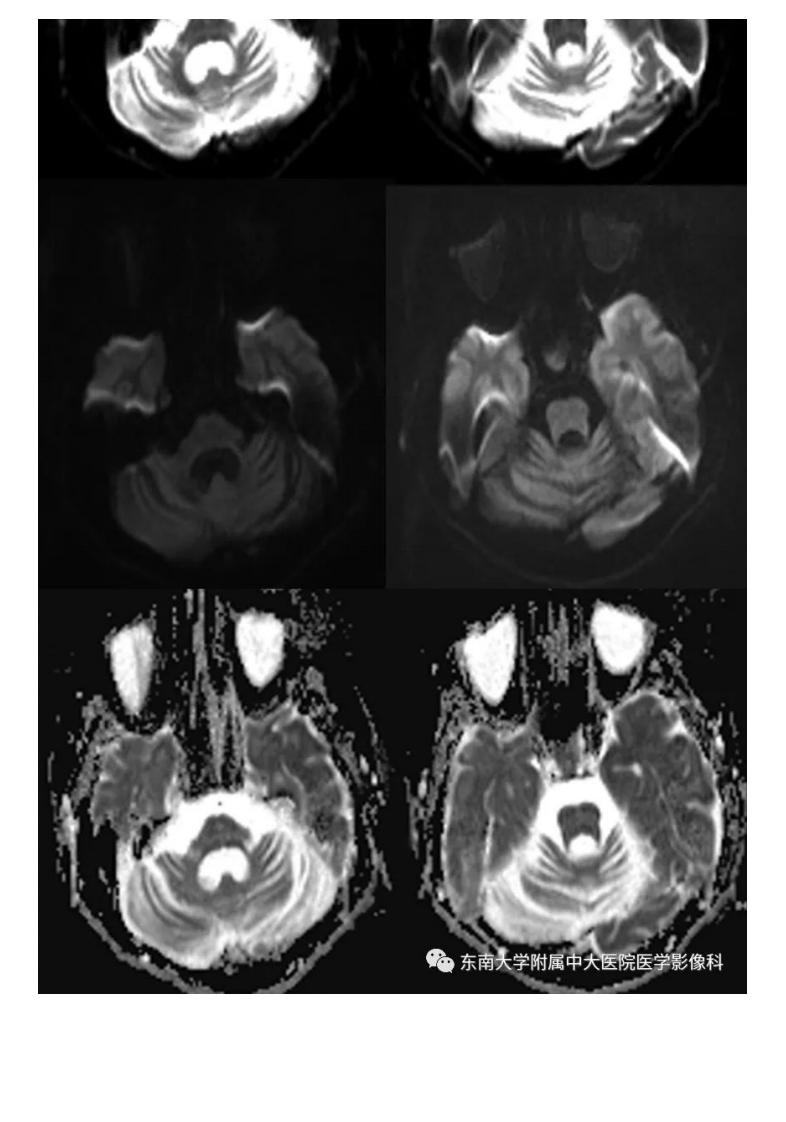

20200928_2【晨读结果公布】2020.09.28神经系统疾病——脊髓小脑性共济失调(病例1).pdf